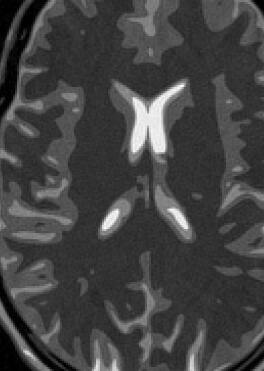

Fig. 14 exhibits the reconstruction results with the spiral trajectory with for . The reconstructed images are displayed alongside profile plots of row . The same is also presented in Figures 13 for .

When sampling on a spiral trajectory, SPURS further demonstrates its superior performance over the other methods. For values high enough, SPURS, NUFFT and rBURS with achieve very good results, but the performance curve for each method levels off for different values of (Figures 9, 10, 11 and 12). Iterative SPURS levels off for values as low as , requiring about iterations to converge to its best result. For these low values, significant artifacts appear in the reconstructed image produced by all methods excluding SPURS as presented in Fig. 13 for and Fig. 14 for . The performance curve of the NUFFT method and of a single iteration of SPURS level off at around . For and higher, a single iteration of SPURS produces marginally better results than those produced by NUFFT, which requires about iterations to converge. Among the other non-iterative methods, both rBURS with and convolutional gridding perform similarly well for , however the results are still inferior to those of a single iteration of SPURS, all of which have similar computational complexity.